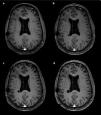

El paciente ha seguido controles mediante RM craneal, y en el estudio realizado en 2017 se detectó una lesión quística de nueva aparición en la corona radiata derecha, objetivándose un crecimiento progresivo en sucesivos controles (fig. 1). La exploración clínica del paciente no mostró ningún déficit o alteración neurológica de nueva aparición. Se trata de una lesión quística y septada, isointensa al LCR en todas las secuencias; sin gliosis ni edema circundante, sin restricción de la difusión ni realce tras la administración de contraste. Está situada en el campo de irradiación, y se encuentra rodeado de múltiples focos hemorrágicos puntiformes, visibles en secuencias de susceptibilidad magnética, en la sustancia blanca adyacente8 (fig. 2).

Imágenes potencias en T1-3D SPGR tras la administración de contraste intravenoso en 4 controles realizados en 2017, 2018, 2019 y 2020 (sucesivamente imágenes a-d). Se aprecia crecimiento progresivo de una lesión redondeada en corona radiada derecha, isointensa al LCR y sin realce parietal.